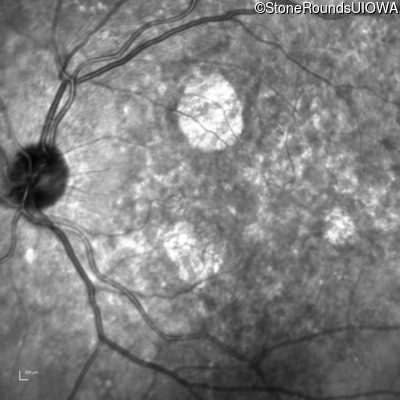

Infrared Fundus Photograph - Right - 20/25 -2

Exemplar